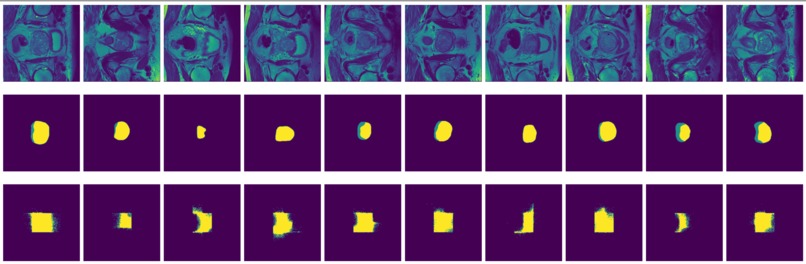

Figure 8: True (top) and predicted (bottom) segmentation from FCN trained with data augmented by flipping and rotation.

-

Figure 9: True (top) and predicted (bottom) segmentation from dilated FCN trained with data augmented by flipping and rotation.

FCN is outperformed by the two encoder-decoder models due to the thin deconvolutional layer as decoder and coarse output in the final deconvolutional layer. The dilated FCN managed to improve performance of FCN but is still outperformed by the encoder-decoder models. For the two encoder-decoder based models, U-Net outperforms DeConvNet in general. This is not surprising since U-Net is specifically designed for medical images and is supposed to achieve higher segmentation accuracy with fewer data. Moreover, randomly flipping input images seems to help improve performance for both of the models. Figure 8 and Figure 9 are the true (top) and predicted (bottom) segmentation of 10 test images from FCN and dilated FCN trained with data augmented by flipping and rotation. Figure 10 and Figure 11 are the true (top) and predicted (bottom) segmentation of 10 test images from DeConvNet and U-Net trained with data augmented by flipping and rotation. It can be seen that U-Net gives a smoother edge than FCN, dilated FCN and DeConvNet.